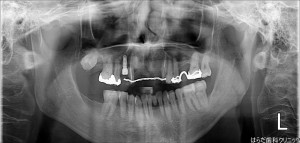

【左上2番1番、左上1番2番】GBR

GBR(骨再生誘導法)のオペでした。

インプラントを埋入するには、必要な骨の厚さがあります。

骨の再生や移植は患者様ごとに先生がCT画像や口腔内を診て相談していきます。